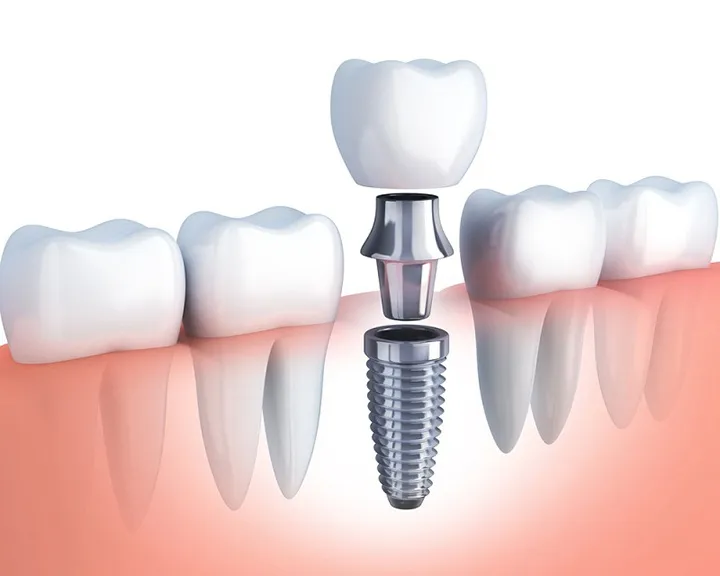

Bước 4: Gắn mão sứ

Trụ Implant tích hợp với xương hàm có thể gắn mão sứ để hoàn thiện quá trình phục hình. Bác sĩ sẽ gắn mão sứ lên trên trụ Implant, kết nối bằng khớp nối Abutment. Mão sứ có màu sắc, kiểu dáng, kích thước tương tự như răng thật. Từ đó đảm bảo tính tương thích với các răng khác trên cung hàm. Sau khi hoàn tất việc gắn mão sứ, bác sĩ sẽ vệ sinh lại răng miệng một lần nữa. Cuối cùng kết thúc quá trình trồng Implant.